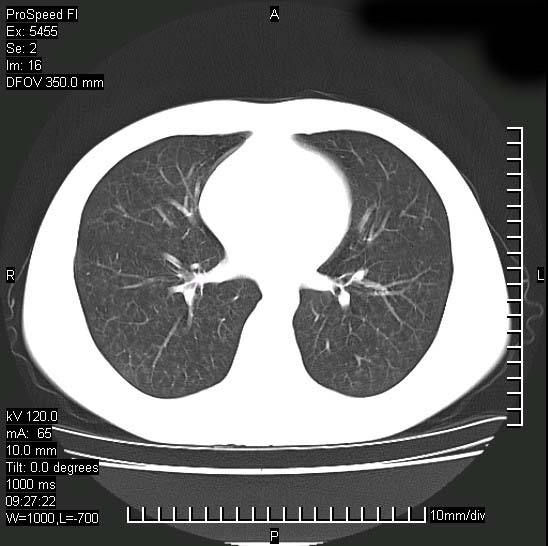

以下是引用zjzjr在2008-12-3 20:50:00的发言:[br]考虑泛细支气管肺炎,建议进一步检查除外肺出血性疾病如含铁血黄素沉着症、肺肾综合征等。

以下是引用zjzjr在2008-12-3 20:50:00的发言:[br]考虑泛细支气管肺炎,建议进一步检查除外肺出血性疾病如含铁血黄素沉着症、肺肾综合征等。

以下是引用光线在2008-12-3 20:19:00的发言:[br]双肺间质性改变。